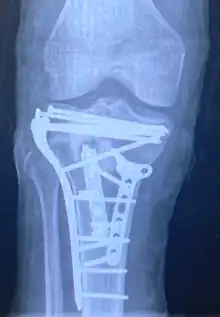

| A severe tibial plateau fracture with an associated fibular head fracture | |